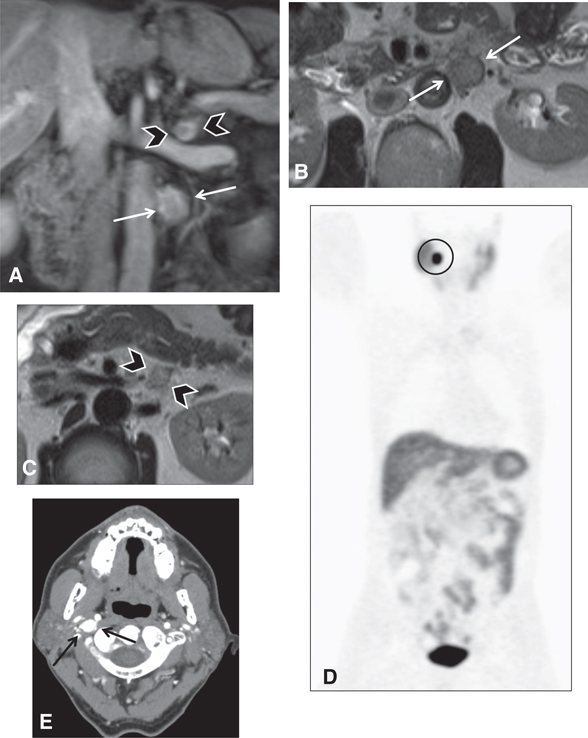

Fig 2

Figure 2 Pheochromocytoma in a 45-year-old male patient. (A) Sagittal and (B) axial ultrasound images of the right adrenal region demonstrate a lesion of heterogeneous echogenicity between the liver (top portion of A and B) and the right kidney (right side of A). The lesion contains a cystic component (asterisk) as well as echogenic foci (arrowheads), suggesting calcifications.